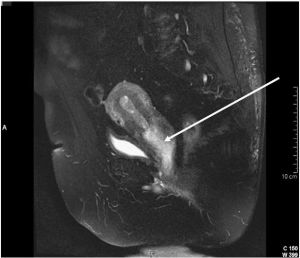

腎錯構瘤又稱腎血管平滑肌脂肪瘤,為良性腫瘤。近年來發病率有增高趨勢,可能與診斷技術水平提高有關。腎錯構瘤可以是獨立的疾病,也可能伴有結節性硬化,後者是常染色體顯性遺傳。臨床特點為雙腎多發病灶,合併智力發育遲緩,面部蝴蝶狀皮脂腺瘤等。女性多見,發病年齡多為20-50歲。但我國腎錯構瘤患者絕大多數並不伴有結節性硬化。肝錯構瘤

腎錯構瘤屬腎實質良性腫瘤,皮質和髓質內均可發生。病理檢查見腫瘤大小不一,可向腎外或集合系統生長,無完整被膜,但界限清楚,切面呈灰白、灰黃或混雜黃色,有的可見出血灶。鏡下見腫瘤由成熟的脂肪組織、血管和平滑肌以不同比例構成,也可混有纖維組織。一般認為,腫瘤出血的主要病理基礎是由於腫瘤含有豐富的血管組織,而這些血管管壁厚薄不一且缺乏彈性,血管行徑迂曲並可成動脈瘤樣改變,受輕微外力打擊即可破裂。